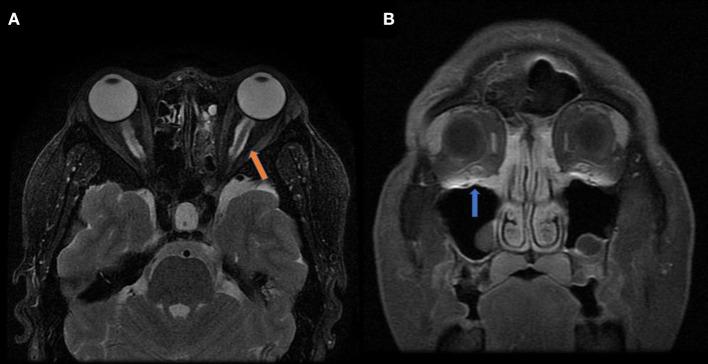

Optic perineuritis (OPN) is a special optic neuropathy that has a distinct etiology from neuromyelitis optica spectrum disorders (NMOSDs) or multiple sclerosis (MS)-related optic neuritis (ON). The mechanisms of how this inflammation developed and invaded the nerve sheath remain unknown. This study is aimed to analyze the etiology and different clinical characteristics of OPN in a Chinese patient population. Neuro-ophthalmological examination, orbit magnetic resonance imaging (MRI) and a series of blood samples were used in this retrospective observational cohort study to compare characteristics of OPN with idiopathic demyelination optic neuritis (IDON). Forty-four OPN cases (74 eyes) and 61 IDON cases (78 eyes) were analyzed. OPN cases included 33 cases (59 eyes) were associated with specific autoimmune diseases, 10 cases (13 eyes) were associated with infection diseases, 1 case was idiopathic disease. The causes of OPN with CTD were Graves' disease, Immunoglobulin G4-related disease (IgG-4 RD), granulomatosis with polyangiitis (GAP), systemic lupus erythematosus (SLE), Sarcoidosis, Rheumatoid arthritis, scleroderma, Behcet's disease, and gout. All patients received orbital MRI. Overall, 33 cases showed orbit fat infiltration. Specifically, nine cases with IgG-4 RD showed trigeminal nerve branch involvement, 12 cases with Graves' disease showed extraocular muscle belly enlargement, and 4 cases with GAP showed pterygopalatine fossa pseudotumor. Compared to IDON patients, OPN patients were older ( = 0.004) and more likely bilateral involvement 26 (78.79%) patients had bilateral involvement in OPN group vs. 17 (27.87%) in the IDON group ( < 0.001). Visual acuity scores using LogMAR testing was better in OPN patients compared to those with IDON, 0.55 ± 0.91 vs. 1.19 ± 1.24 ( < 0.001). Other ophthalmologic findings unique to the OPN group include 11 (33.33%) cases of ptosis, nine (27.27%) cases of diplopia, and 10 (30.30%) cases of exophthalmos, compared to zero cases of these conditions in the IDON group. Eight (13.11%) IDON patients also had multiple sclerosis (MS) and 7 (11.48%) patients had neuromyelitis which was significantly more than the zero patients in OPN group ( = 0.04). OPN had distinct etiologies and clinical characteristics from IDON and is more often associated with autoimmune diseases. Using OPN characteristics to diagnose autoimmune diseases should prove useful for clinicians when presented with patients that have multiorgan dysfunction that include ophthalmologic findings.

视神经周围炎(OPN)是一种特殊的视神经病变,其病因与视神经脊髓炎谱系障碍(NMOSD)或多发性硬化(MS)相关的视神经炎(ON)截然不同。这种炎症如何发展并侵犯神经鞘的机制尚不清楚。本研究旨在分析中国患者群体中OPN的病因及不同临床特征。在这项回顾性观察队列研究中,采用神经眼科检查、眼眶磁共振成像(MRI)和一系列血液样本,以比较OPN与特发性脱髓鞘性视神经炎(IDON)的特征。分析了44例OPN患者(74只眼)和61例IDON患者(78只眼)。OPN病例包括33例(59只眼)与特定自身免疫性疾病相关,10例(13只眼)与感染性疾病相关,1例为特发性疾病。与结缔组织病(CTD)相关的OPN病因包括格雷夫斯病、免疫球蛋白G4相关性疾病(IgG-4 RD)、肉芽肿性多血管炎(GAP)、系统性红斑狼疮(SLE)、结节病、类风湿关节炎、硬皮病、白塞病和痛风。所有患者均接受了眼眶MRI检查。总体而言,33例显示眼眶脂肪浸润。具体而言,9例IgG-4 RD患者显示三叉神经分支受累,12例格雷夫斯病患者显示眼外肌肌腹增大,4例GAP患者显示翼腭窝假瘤。与IDON患者相比,OPN患者年龄更大(P = 0.004),双侧受累的可能性更高,OPN组26例(78.79%)患者双侧受累,而IDON组为17例(27.87%)(P < 0.001)。使用LogMAR测试的视力评分在OPN患者中优于IDON患者,分别为0.55±0.91和1.19±1.24(P < 0.001)。OPN组特有的其他眼科表现包括11例(33.33%)上睑下垂、9例(27.27%)复视和10例(30.30%)眼球突出,而IDON组这些情况均为零例。8例(13.11%)IDON患者还患有多发性硬化(MS),7例(11.48%)患者患有视神经脊髓炎,这显著多于OPN组的零例患者(P = 0.04)。OPN与IDON有不同的病因和临床特征,且更常与自身免疫性疾病相关。当面对有多器官功能障碍并伴有眼科表现的患者时,利用OPN的特征来诊断自身免疫性疾病对临床医生应是有用的。